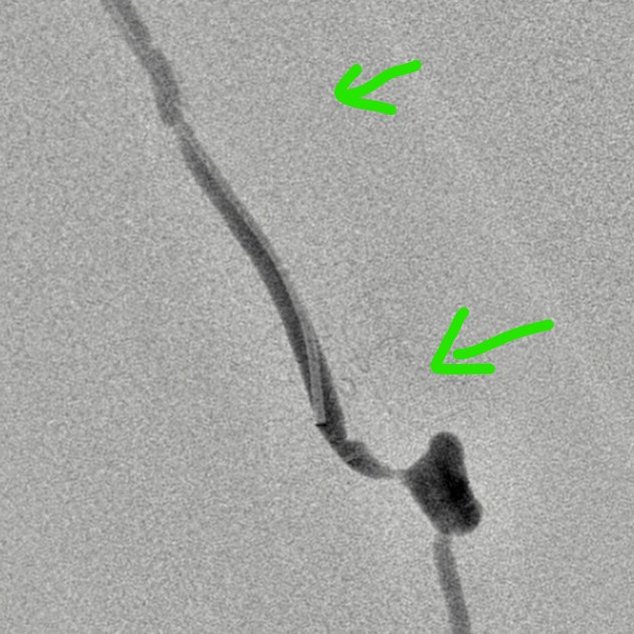

MRI/CT interpretation and Thrombectomy and stenting/ plasty for acute and recurrent stroke. Cerebral DSA

Thrombectomy – mechanical , pharmacological and combined therapy for acute stroke.

Outcomes observed in patients treated with image-guided, minimally invasive vascular procedures.

Results vary by patient and condition. Images are for educational purposes only.